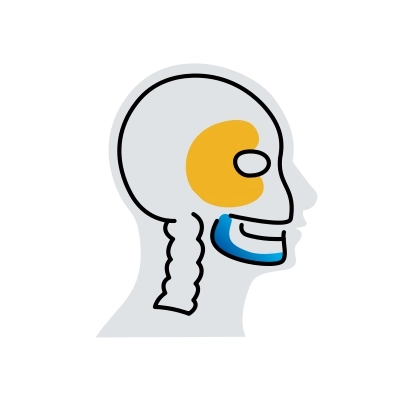

Sistema de Artroplastia Total da ATM

Nosso dispositivo médico personalizado ou standard, cirurgicamente invasivo e implantável, é composto por um componente temporal e um mandibular, para restaurar a articulação temporomandibular (ATM).